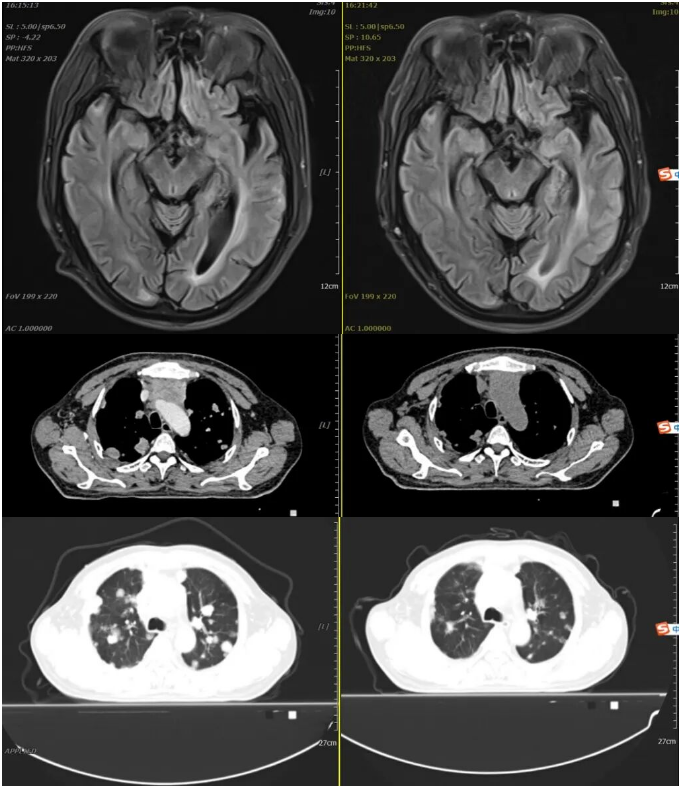

2023-01-30 2023-03-03

2023年1月30日开始口服“马来酸阿法替尼片(自带)40mg 口服 qd”靶向治疗。

2023年3月3日我院复查胸腹盆平扫CT、头颅平扫MR:疗效评估:SD(病情稳定)